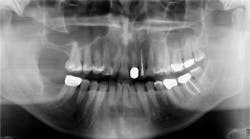

When a radiograph is taken, the dental professional may see what appears to be the outline of the root socket where an extraction has occurred, usually many years prior to any complaints (figures 1 and 2). This is a residual socket or residual root socket. The outline of the tooth’s root cavity is faintly visible, and when examined surgically, it may be hollow or filled with dense fibrous scar tissue, granulation tissue, or very immature bone.

Figure 1: Residual sockets. Note the outline of the previous roots of the molar tooth. Courtesy of Jerry E. Bouquot, DDS, MSD, DABOMP, DABOM (hon), FAAOMP, FICD, FACD, FRCM (UK), emeritus professor and past chair, Department of Diagnostic and Biomedical Sciences, University of Texas, Houston, Texas.